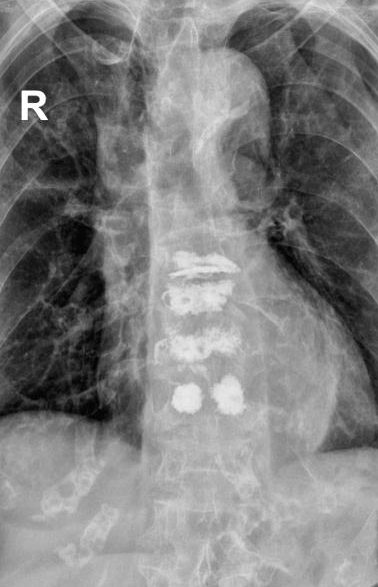

术中,负责人贺毅及团队在C型臂X线透视下,避开神经血管,通过4个3mm的小切口将穿刺针精准抵达骨折部位T9和T11,注入“骨水泥”强化椎体,术中严格控制骨水泥灌注速度与剂量,避免渗漏风险。全程局麻,李奶奶意识清醒,无痛感,出血不足5毫升,术后李奶奶疼痛评分从8分骤降至2分,次日即在支具保护下自主行走,顺利出院。